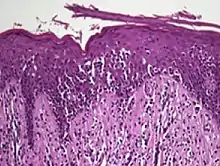

The criteria for the disease are established on the skin biopsy:[10]

- the superficial papillary dermis is infiltrated by a bandlike lymphocyte infiltrate

- epidermotropism

- presence of atypical T-cells with cerebriform nuclei in the dermal and epidermal infiltrates.

Pautrier's microabcesses are aggregates of four or more atypical lymphocytes arranged in the epidermis.[11] Pautrier microabcesses are characteristic of mycosis fungoides but are generally absent.

Traditionally, mycosis fungoides has been divided into three stages: premycotic, mycotic and tumorous. The premycotic stage clinically presents as an erythematous (red), itchy, scaly lesion. Microscopic appearance is non-diagnostic and represented by chronic nonspecific dermatosis associated with psoriasiform changes in epidermis.

In the mycotic stage, infiltrative plaques appear and biopsy shows a polymorphous inflammatory infiltrate in the dermis that contains small numbers of frankly atypical lymphoid cells. These cells may line up individually along the epidermal basal layer. The latter finding if unaccompanied by spongiosis is highly suggestive of mycosis fungoides. In the tumorous stage a dense infiltrate of medium-sized lymphocytes with cerebriform nuclei expands the dermis.